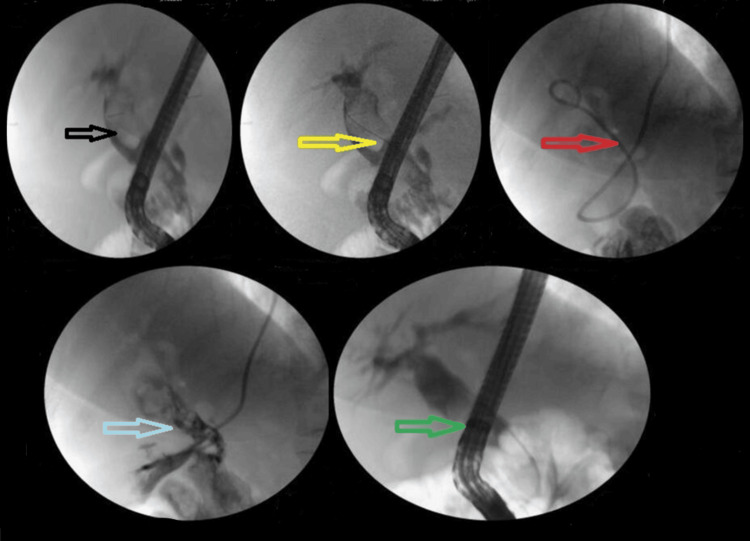

The addition of ML to EPLBD and endoscopic sphincterotomy resulted in an overall success rate of 625/682 (91.6%). Figure 3 illustrates ML used in a patient. The addition of ESWL (Figure 4) resulted in an overall success rate of 638/682 (93.5%), and the addition of EHL resulted in an overall success rate of 650/682 (95.3%) for the endoscopic removal of stones (Figure 5).

ESWL is a valuable adjunctive treatment for difficult CBDS [ref. 25,ref. 26]. Our study focused on patients with large (>2 cm) and hard stones resistant to endoscopic extraction and ML. Consistent with existing literature [ref. 9], our results show ESWL to be highly effective, with an 88% stone clearance rate and no major complications.

ESWL uses electrohydraulic energy to break up bile duct stones under fluoroscopy guidance [ref. 9]. The procedure has a stone clearance rate of 84.4-90.2% [ref. 9,ref. 25,ref. 26]. However, it has limitations, including the need for an NBT or a T-tube, multiple sessions, and anesthesia [ref. 9,ref. 25]. Complications occur in 9.1-15.9% of cases, including hemobilia and cardiac arrhythmia [ref. 9,ref. 25,ref. 26]. The European Society of Gastrointestinal Endoscopy recommends ESWL when conventional lithotripsy fails and cholangioscopy-guided lithotripsy is not available [ref. 6].